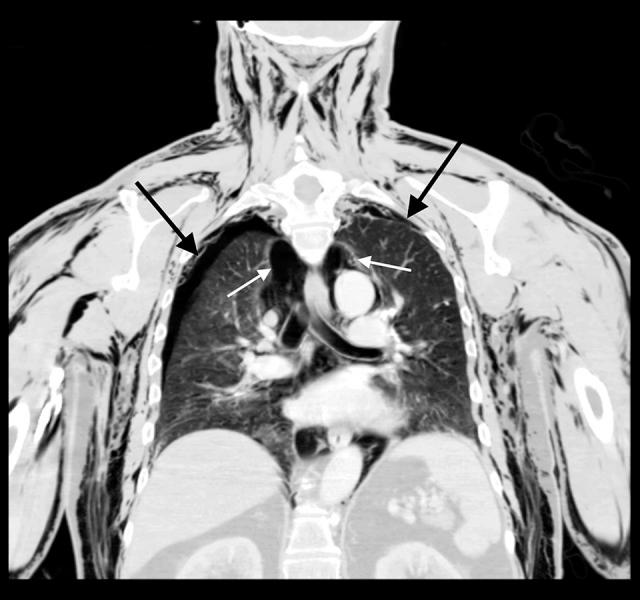

BACKGROUND Pneumoscrotum is a rare clinical occurrence in which air accumulates in the scrotum. The origin of air is primarily from trauma, but spontaneous pneumoscrotum can develop from gastrointestinal or pulmonary sources. Physical examination of pneumoscrotum typically includes crepitus of the perineal region and scrotal swelling and associated findings depending on the origin of the free air. However, pneumoscrotum in the setting of a scrotal wound, which allows air to pass freely outside the body, has not been previously documented in the literature. CASE REPORT A 72-year-old man who recently underwent a scrotal incision and drainage for recurrent epididymitis presented to a local emergency room with chief concerns of "whistling scrotum" and dyspnea. The chest CT revealed bilateral pneumothoraces, pneumomediastinum, and excessive subcutaneous emphysema throughout his abdomen, perineum, and scrotum. His scrotum had a dehiscent wound without any gross edema or air trapping contained within the scrotum. He received bilateral chest tubes and subcutaneous air drains with complete resolution of his pneumothoraces. The pneumoscrotum and associated subcutaneous emphysema of the perineum and thighs resolved after a prolonged period, and necessitated additional scrotal surgery. CONCLUSIONS Prompt evaluation for source control is necessary with pneumoscrotum, as the source likely requires immediate stabilization or surgical intervention. This case report describes a unique presentation of a common entity (pneumothorax) within pulmonology/critical care in a patient with an open scrotal wound from a recent scrotal procedure, which allowed the air to escape from his abdominal compartment, and resulted in his "scrotal whistling." It is unclear how the air passing through the scrotum affected the patient's presentation, such as allowing more air to build up in the subcutaneous tissues versus developing critical illness.

一名 72 岁的男性最近因复发性附睾炎接受了阴囊切开引流术,他因“哨子阴囊”和呼吸困难到当地急诊室就诊。胸部 CT 显示双侧气胸、纵隔气肿和整个腹部、会阴和阴囊过度皮下气肿。他的阴囊有一个裂开的伤口,阴囊内没有明显的肿胀或空气滞留。他接受了双侧胸腔引流管和皮下空气引流管治疗,气胸完全缓解。阴囊气肿和会阴及大腿的相关皮下气肿在长时间后才得到解决,并且需要进行额外的阴囊手术。